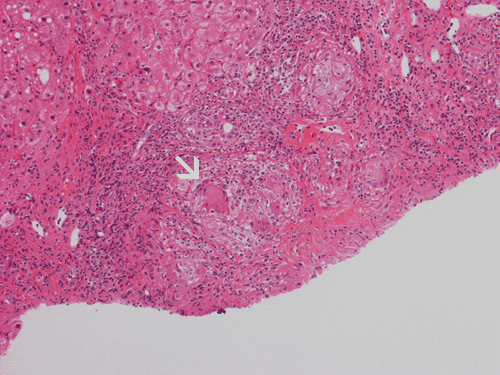

Pathology of the Case: At low magnification, a few small nodules (arrow in Panel A) can be seen with the hematoxylin and eosin stained section. On medium magnification, these nodules correspond to sharply defined granuloma without necrosis. These granuloma are not associated with a high density of lymphocytes in the surrounding liver parenchyma (Panel B and C). Multinucleated giant cells (arrow in Panel C, magnified in Panel D). On reticulin stain, there are reticulin fibers that extends into the granuloma (Panel E). Trichrome stain demonstrated bridging fibrosis (Panel F). The granuloma are well defined and some of them are surrounded by fibrous tissue (Panel G). Immunohistochemistry demonstrated preservation of bile ductules as well as proliferation of ductules (Panle H). No residual ductules are noted in the granuloma as revealed by immunohistochemistry for CK7 (Panel I). Neither acid fast bacilli or fungal organisms are identified by acid fast stain and Gomori's methenamine silver (GMS) stain.

Histopathologic features of sarcoidosis include scattered granulomas in the liver, which may tend to be portal or periportal. Multinucleated giant cells, epithelioid cells, and a variable but usually minimal inflammatory cellular response is present. The granulomas, like in sarcoidosis occuring in other organ systems, tend to be well-demarcated or "clear cut", several granulomas are often comparable in size, and necrosis is not typically present. Asteroid bodies, intracellular vacuolated structures resembling a sea anemone, may be found within the giant cells. Large basophilic, round to roughly oval, and concentrically laminated, Schaumann bodies may be evident in the sarcoid granuloma. None of these inclusions are pathognomonic feature of sarcoidosis, however, do suggest this diagnosis. Ductopenia, cholestasis and features of chronic cholestasis resembling PBC have been described in the cases of sarcoidosis. Severe fibrosis and cirrhosis in conjunction with portal hypertension may be present in sarcoidosis. End stage liver disease in sarcoidosis has been successfully treated by orthotopic liver transplant and recurrent disease has been reported in one such case. Reticulin fibers has a tendency to extend into the granulomas as illustrated in this case.